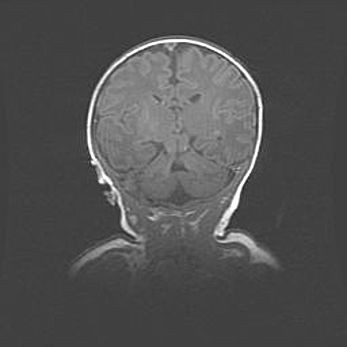

Сообщающаяся гидроцефалия. Кистозная энцефаломаляция головного мозга.

Возраст: 3 месяца 4 дня

Вес: 3100 г

Пол: женский

Окружность головы: 34 см

Срок гестации: 31 неделя

Кистозная энцефаломаляция головного мозга - одна из форм поражения головного мозга в детском возрасте. Характеризуется возникновением множественных и распространённых кист в коре, белом веществе и подкорковых образованиях головного мозга у плодов, новорождённых и детей раннего возраста. Развитие кистозной энцефаломаляции связано с внутриутробной асфиксией и гипотонией, родовой травмой, тромбозом синусов, пороками развития сосудов, инфекциями, сепсисом и другими причинами. Наиболее значимые инфекционные агенты: вирусы простого герпеса, цитомегалии, краснухи, токсоплазмы, энтеробактерии, золотистый стафилококк и другие.